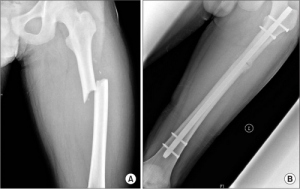

Если скелетное вытяжение не позволяет правильно сопоставить костные отломки, назначают оперативное лечение. Его нужно применять рано, на второй-пятый день после травмы. Трудно вправляются надмыщелковые, подвертельные и поперечные переломы диафиза бедренной кости. Чаще всего остеосинтез проводят с помощью гвоздя, иногда применяют металлические пластинки.

Оперативное лечение

Антеградный интрамедуллярный остеосинтез закрытых диафизарных переломов бедра. Эта операция выполняется с применением общего обезболивания. Репозиция делается на ортопедическом столе. Все выполняется под рентгенологическим контролем. Лучше всего применять электронно-оптический преобразователь.

Там, где располагается вершина большого вертела, делается продольный широкий разрез кожного покрова, клетчатки и фасции. По ходу раны нужно раздвинуть волокна ягодичных мышц и напрягателя широкой фасции. Вершина главного вертела обнажается. Сначала нужно сформировать канал на внутренней стороне вертела. Это делается с помощью специального шила. Через канал вводят проводник, который проводится в дистальный фрагмент.

По проводнику нужно забить стержень Кюнчера. Его длину определят по здоровому бедру. Дистальный конец штифта размещается на три или четыре сантиметра проксимальнее щели сустава. Нельзя допускать, чтобы проксимальный конец выступал более чем на один сантиметр над вершиной главного вертела. Рана ушивается послойно. На сутки устанавливается дренаж, а конечность без вытяжения оставляют на шине Белера. После того как рана заживет больной может ходить на костылях. Стержень удаляется через год, если есть все признаки консолидации.

Ретроградный интрамедуллярный остеосинтез с помощью массивного четырехгранного штифта ЦИТО. Для того чтобы выполнить закрытый остеосинтез при переломах диафиза бедренной кости может понадобиться больше времени, что в случае с открытым остеосинтезом. Очень важно соблюдать все требования антисептики.

Сначала делают разрез кожи и клетчатки. При этом врач ориентируется по уровню перелома и диафизу бедра. Длина разреза составляет от 15 до 20 сантиметров. Рана должна быть изолирована от кожных покровов. По ходу раны рассекается широкая фасция бедра. Разъединяются волокна четырехглавой бедренной мышцы. Все рассеченные сосуды прошиваются. В месте перелома освобождают дистальный отломок с помощью широкого распаратора. Отломок поднимают и острым однозубым крючком выводят в рану. Затем под него вводят салфетку-держалку. То же самое делают с проксимальным отломком.

Диаметр штифта ЦИТО подбирают индивидуально. Для его введения нужно рассверлить костномозговой канал. Развертка должна быть проникнута в вертельную ямку. Четырехгранный штифт забивается в проксимальный отломок ретроградным путем. Диаметр сверла должен соответствовать диаметру штифта. Если канал слишком узкий, может случиться заклинивание штифта, а также перелом диафиза. Штифт не должен касаться кожи, поэтому используются специальную «ложку». Отломки репонируют и удерживают костодержателями. Штифт забивается дистальный отломок с помощью специальной насадкой. Чтобы не произошло разобщение костных отломков по длине, помощник хирурга должен обеспечить противоупор. Рана ушивается послойно. На сутки устанавливается дренаж.

Другие оперативные методы включают остеосинтез пластинами и внешнюю фиксацию. Закрытое лечение с использованием вытяжения, шинирования и гипсования может быть временным или постоянным в некоторых странах третьего мира. Интрамедуллярный остеосинтез (ИМН) является золотым стандартом лечения переломов диафиза бедренной кости.